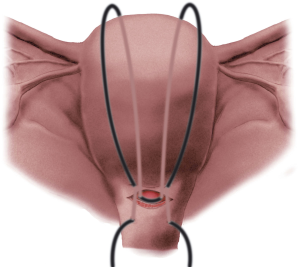

55f28d9715bbdff6.PK_2a_1

f559648e926da6e6.PK_3a_1